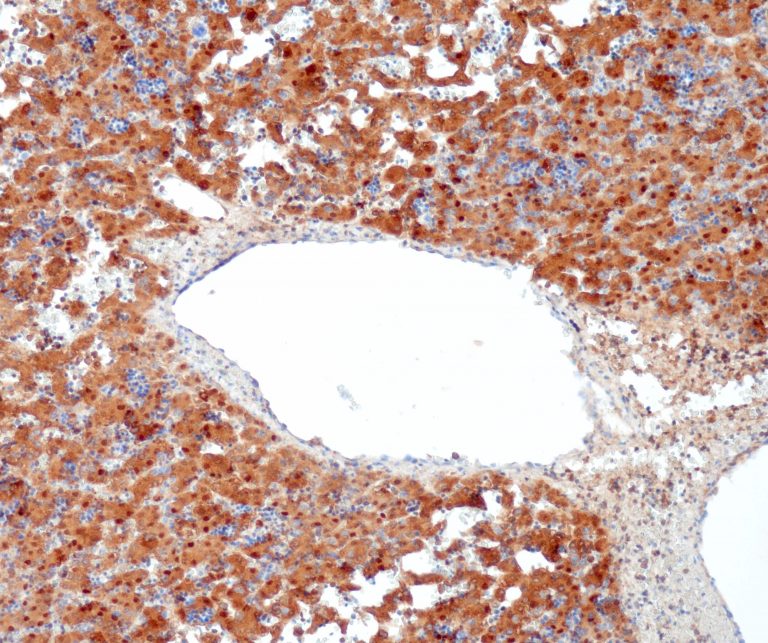

Vascular Pathology

Gastrointestinal (GI) Pathology

General Marker

Breast Pathology

Endocrine Pathology

Gynecological Pathology

Neuropathology

Infection Markers

Lung Pathology

Urinary Tract Pathology

Transplantation Pathology

Soft Tissue Pathology

Hematopathology